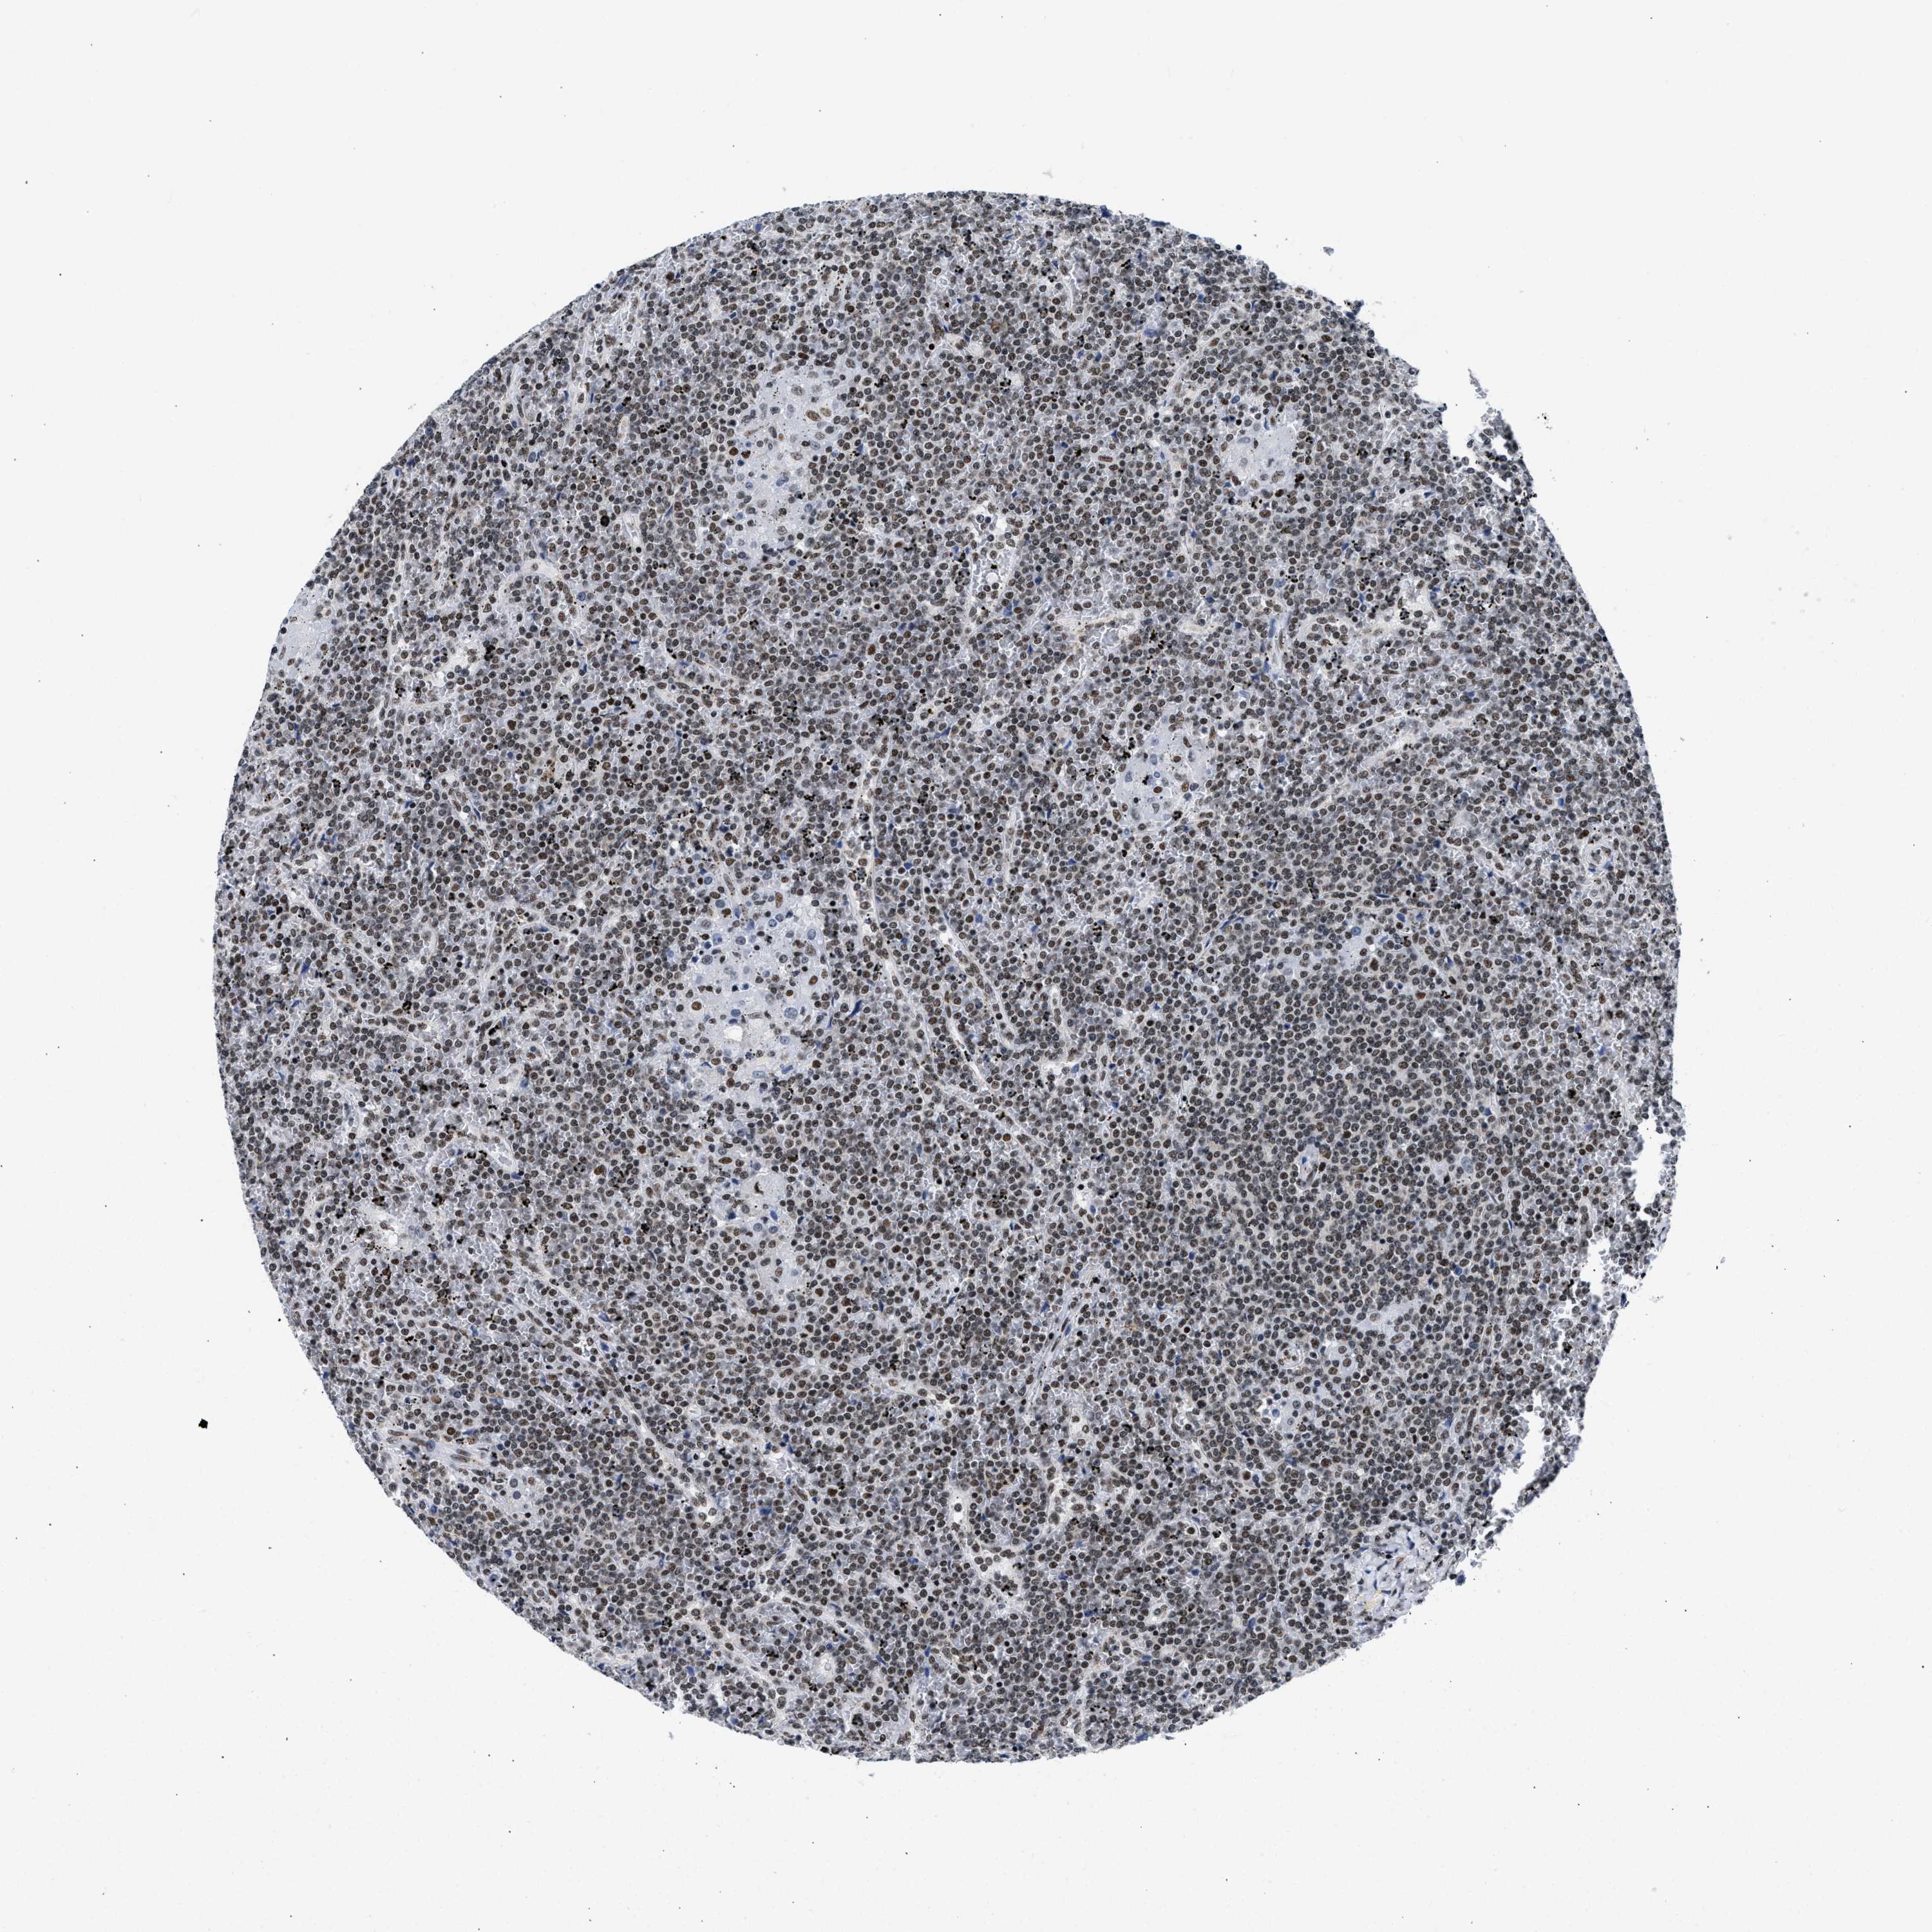

LYMPHOMA - Protein expressioni

A mouse-over function shows sample information and annotation data. Click on an image to view it in a full screen mode. Samples can be filtered based on level of antibody staining by selecting one or several of the following categories: high, medium, low and not detected. The assay and annotation is described here.

Antibody stainingi

Antibody staining in the annotated cell types in the current human tissue is reported as not detected, low, medium, or high, based on conventional immunohistochemistry profiling in selected tissues. This score is based on the combination of the staining intensity and fraction of stained cells.

Each image is clickable and will lead to virtual microscopy that enables deeper exploration of all samples and also displays staining intensity scores, fraction scores and subcellular localization as well as patient and tissue information for each sample.

Antibody HPA018403

Staining

High

Medium

Low

Not detected

Intensity

Strong

Moderate

Weak

Negative

Quantity

>75%

75%-25%

<25%

None

Location

Nuclear

Cytoplasmic/membranous

Cytoplasmic/membranous,nuclear

Hodgkin's disease, NOS

Malignant lymphoma, non-Hodgkin's type, High grade

Malignant lymphoma, non-Hodgkin's type, Low grade